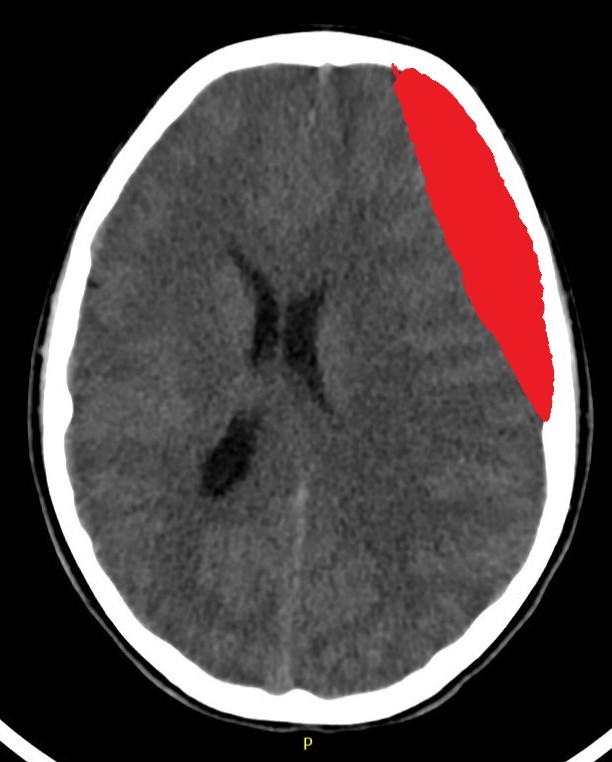

Subdural Hemorrhage

This is a Subdural Hemorrhage (SDH). When blood collects between the outermost membranes surrounding your brain, it takes the shape of a crescent. This often happens when veins that cross this area are torn. This type of bleeding requires close monitoring. If the bleeding continues or the clot grows larger, it may require an operation to remove the blood and relieve the pressure on your brain.